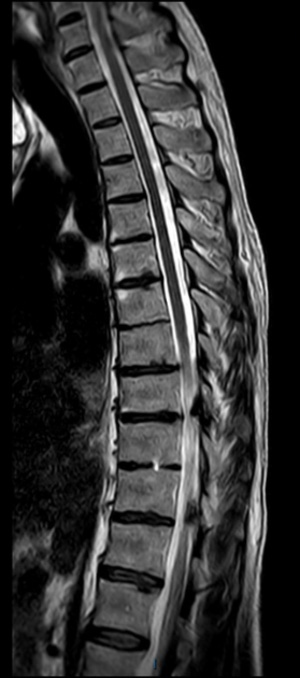

Chụp cộng hưởng từ (MRI) là kỹ thuật chẩn đoán hình ảnh không xâm lấn, cho phép tạo ra hình ảnh chi tiết các cấu trúc bên trong cơ thể, bao gồm các cơ quan, xương, cơ và mạch máu. Máy MRI là một thiết bị lớn, hình trụ, sử dụng từ trường mạnh và sóng radio để tạo ra hình ảnh, không sử dụng bức xạ ion hóa như chụp X-quang.

Từ trường này khiến các nguyên tử trong cơ thể sắp xếp theo cùng một hướng. Sau đó, máy phát ra các xung sóng radio, làm thay đổi hướng của các nguyên tử này. Khi sóng radio tắt, các nguyên tử trở về vị trí ban đầu và phát ra tín hiệu radio. Các tín hiệu này được máy vi tính xử lý để tạo ra hình ảnh chi tiết của bộ phận cơ thể cần khảo sát. Hình ảnh này được hiển thị trên màn hình để bác sĩ quan sát và phân tích.

Chụp MRI có thể được sử dụng để chẩn đoán các vấn đề về khớp, gồm:

Sau đây là một số hình ảnh viêm cột sống dính khớp trên X-quang: